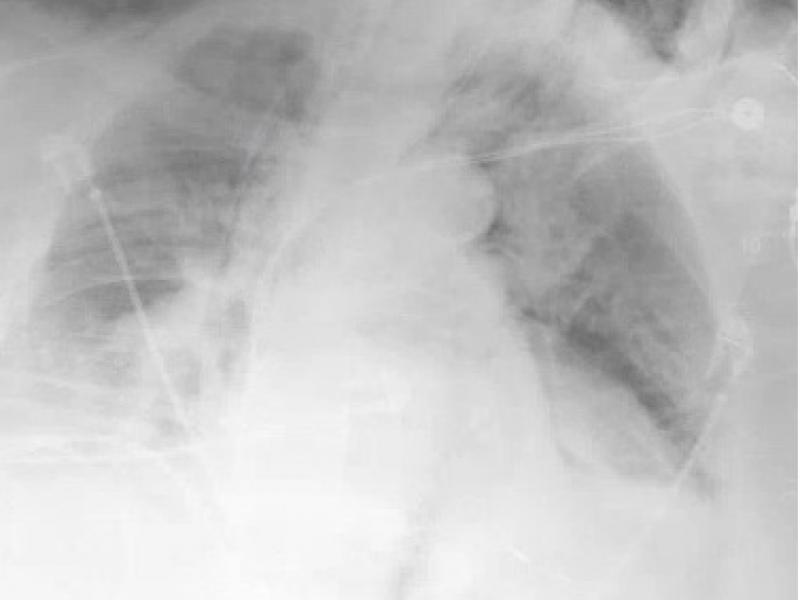

A 71 yo male with a history of esophageal varices c/o severe